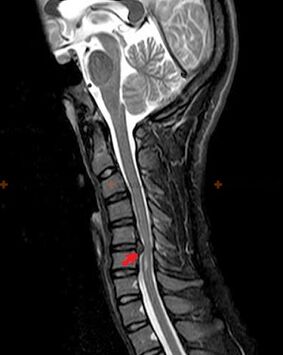

Osteochondrosis is a radiological diagnosis, since a detailed clinical picture is available only at the time of exacerbation, while changes in the spine can occur with the complete subjective well-being of a person.Without X-ray examination, we can only talk about a suspicion of osteochondrosis, since similar symptoms can be provoked by other diseases (myositis, vertebral neoplasms and others).

To diagnose osteochondrosis, the following research methods are used: radiography (preferably with functional tests), MSCT and MRI.The latter study is the most preferable because it allows you to very clearly visualize the state of the intervertebral structures.

The presence of the changes described above, as well as changes in the structure of the intervertebral disc, detected by MSCT and MRI, are reliable signs confirming the presence of osteochondrosis.